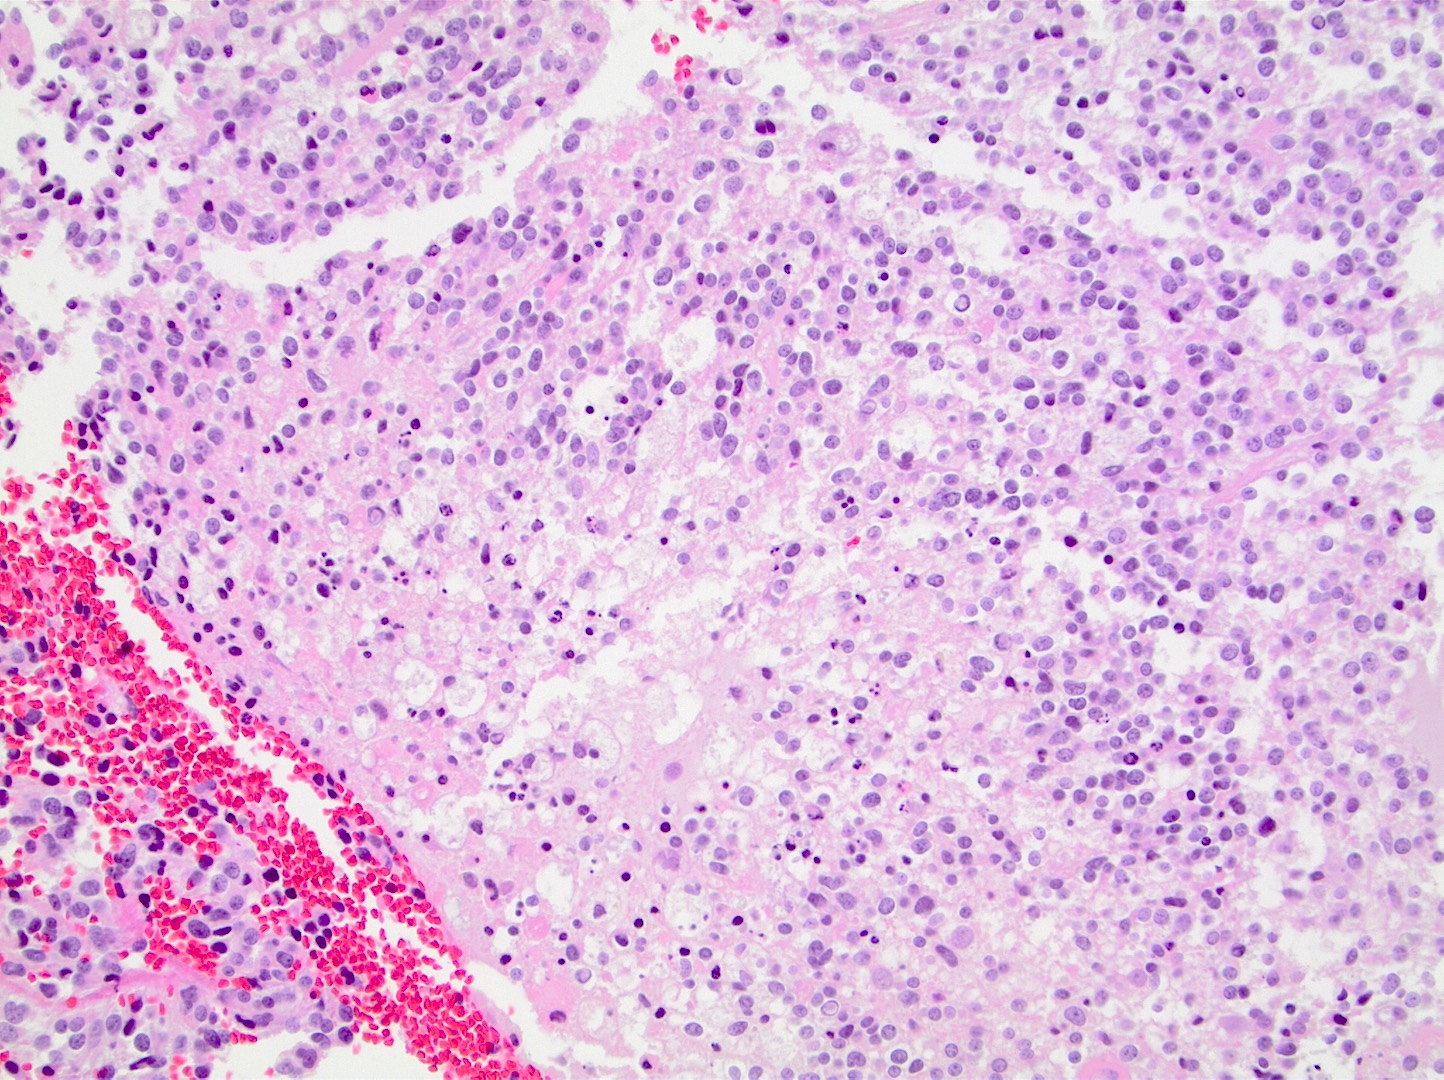

Microscopic (histologic) description

- Closely packed cells with small, round, monotonous nuclei (slightly larger than a normal oligodendrocyte)

- Perinuclear clearing (fried egg appearance)

- Formalin fixation artifact

- Will not be seen on frozen sections or smear preparations

- Network of thin walled, branching blood vessels (chicken wire vasculature)

- Microcalcifications (calcospherites) are characteristic

- Presence of perineural, perivascular or subpial aggregates of tumor cells (secondary structures of Scherer)

- Occasional mitoses and moderate nuclear atypia are still consistent with grade 2 designation (J Neuropathol Exp Neurol 2001;60:248)

- Not uncommon to find well differentiated / fibrillary astrocytic morphology (Acta Neuropathol 1984;64:265)

Microscopic (histologic) images

Contributed by Jared T. Ahrendsen, M.D., Ph.D. and John DeWitt, M.D., Ph.D.